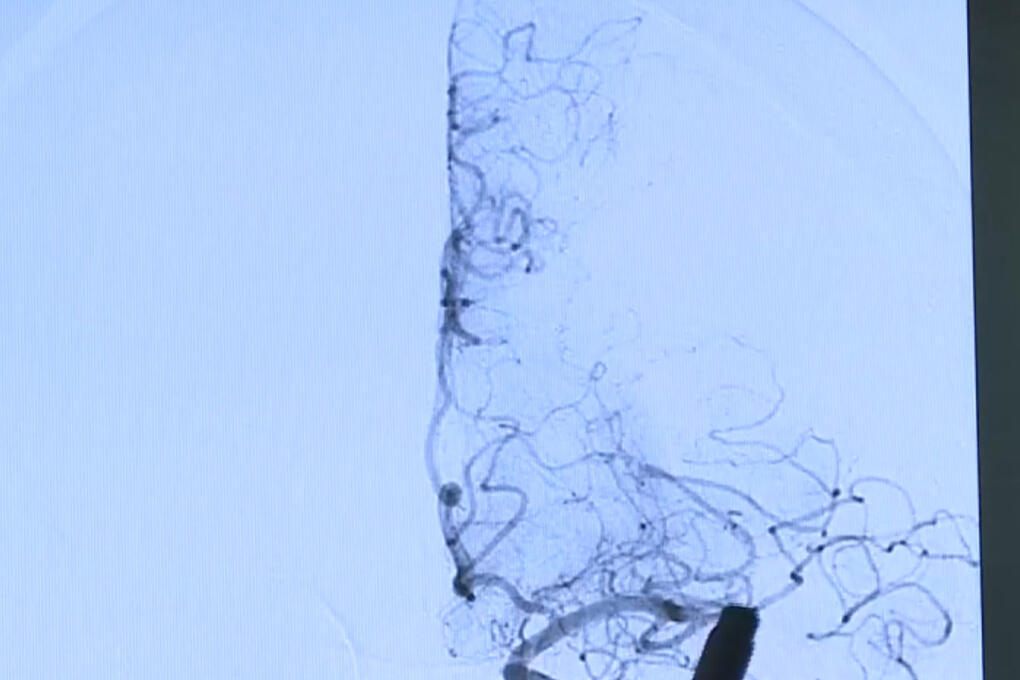

Фото: ГТРК Смоленск

Смоленская область принимает участие в Неделе сохранения здоровья головного мозга.

Врачи отмечают важность профилактики различных заболеваний мозга, включая нервно-мышечные заболевания, эпилепсию, рассеянный склероз, болезнь Паркинсона, деменции, хроническую ишемию головного мозга и инсульт.